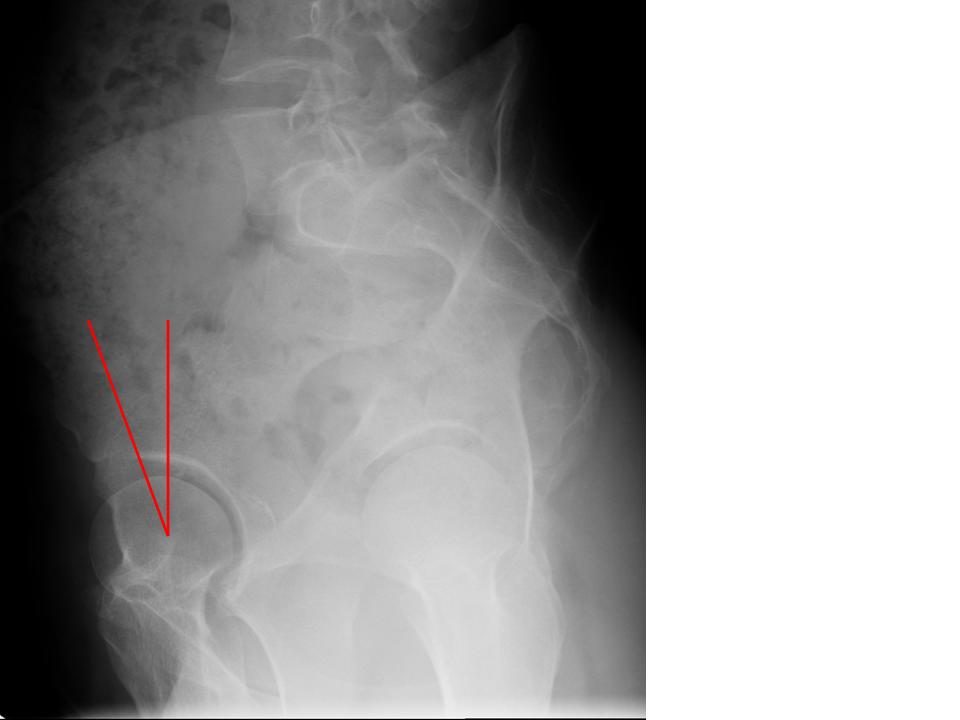

Schematic diagram of normal hip and Crowe’s classifications for adult Hip Dysplasia Orthobullets learn how to perform a comprehensive hip physical exam on adult patients, including inspection, palpation, neurovascular, rom, and. developmental dysplasia of the hip (ddh) is a condition where the hip joint does not form normally, causing the thighbone to be loose or dislocated in the socket. a review article on the epidemiology, pathomechanism, diagnosis, and treatment of. Hip Dysplasia Orthobullets.